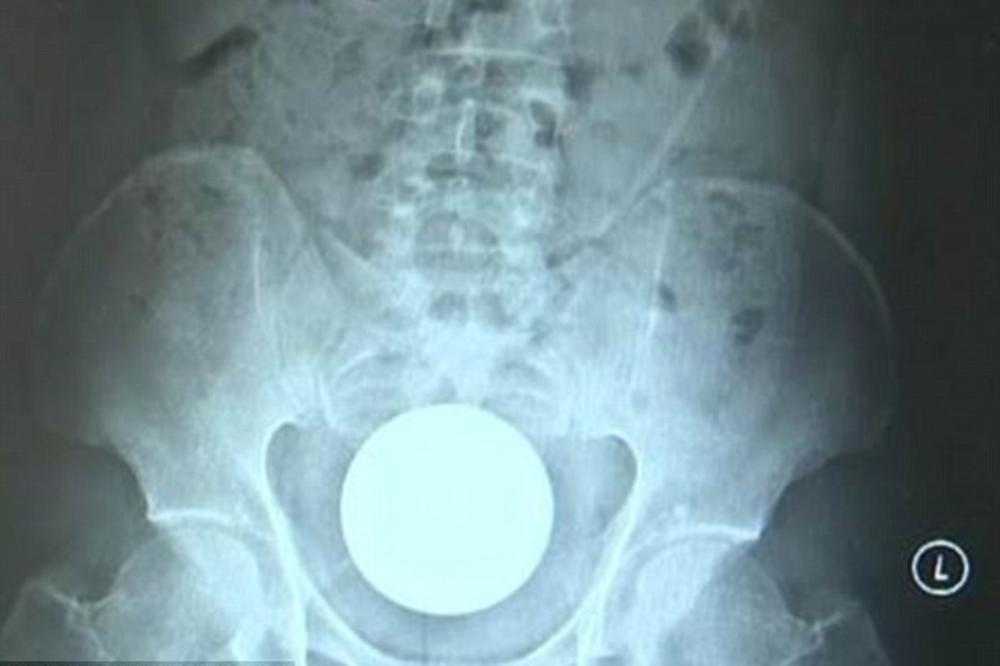

Jedan Kinez završio je u bolnici nakon što je sebi u rektum gurnuo staklenu kuglu prečnika 8 centimetara.

Muškarac (31) žalio se na užasne bolove pošto je staklo u njemu ostalo zaglavljeno nekoliko sati.

Doktori su uspeli da izvuku staklo tek posle operacije koja je trajala preko sat vremena. Muškarac je bio u opasnosti da doživi septički šok, ali je kugla izvađena na vreme.